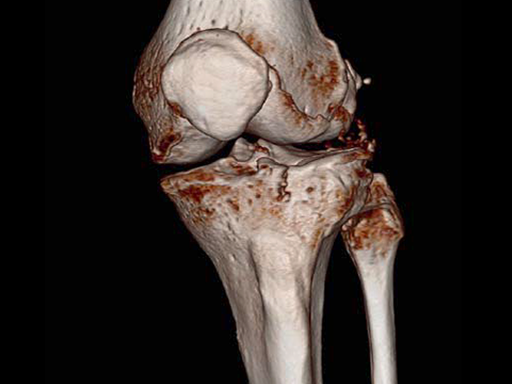

A 70-year-old female patient had an accident while hiking. Osteoporosis was preexisting but with asymptomatic moderate degenerative osteoarthritis of the knee with chondrocalcinosis of the lateral compartment (Fig 1 and 2).